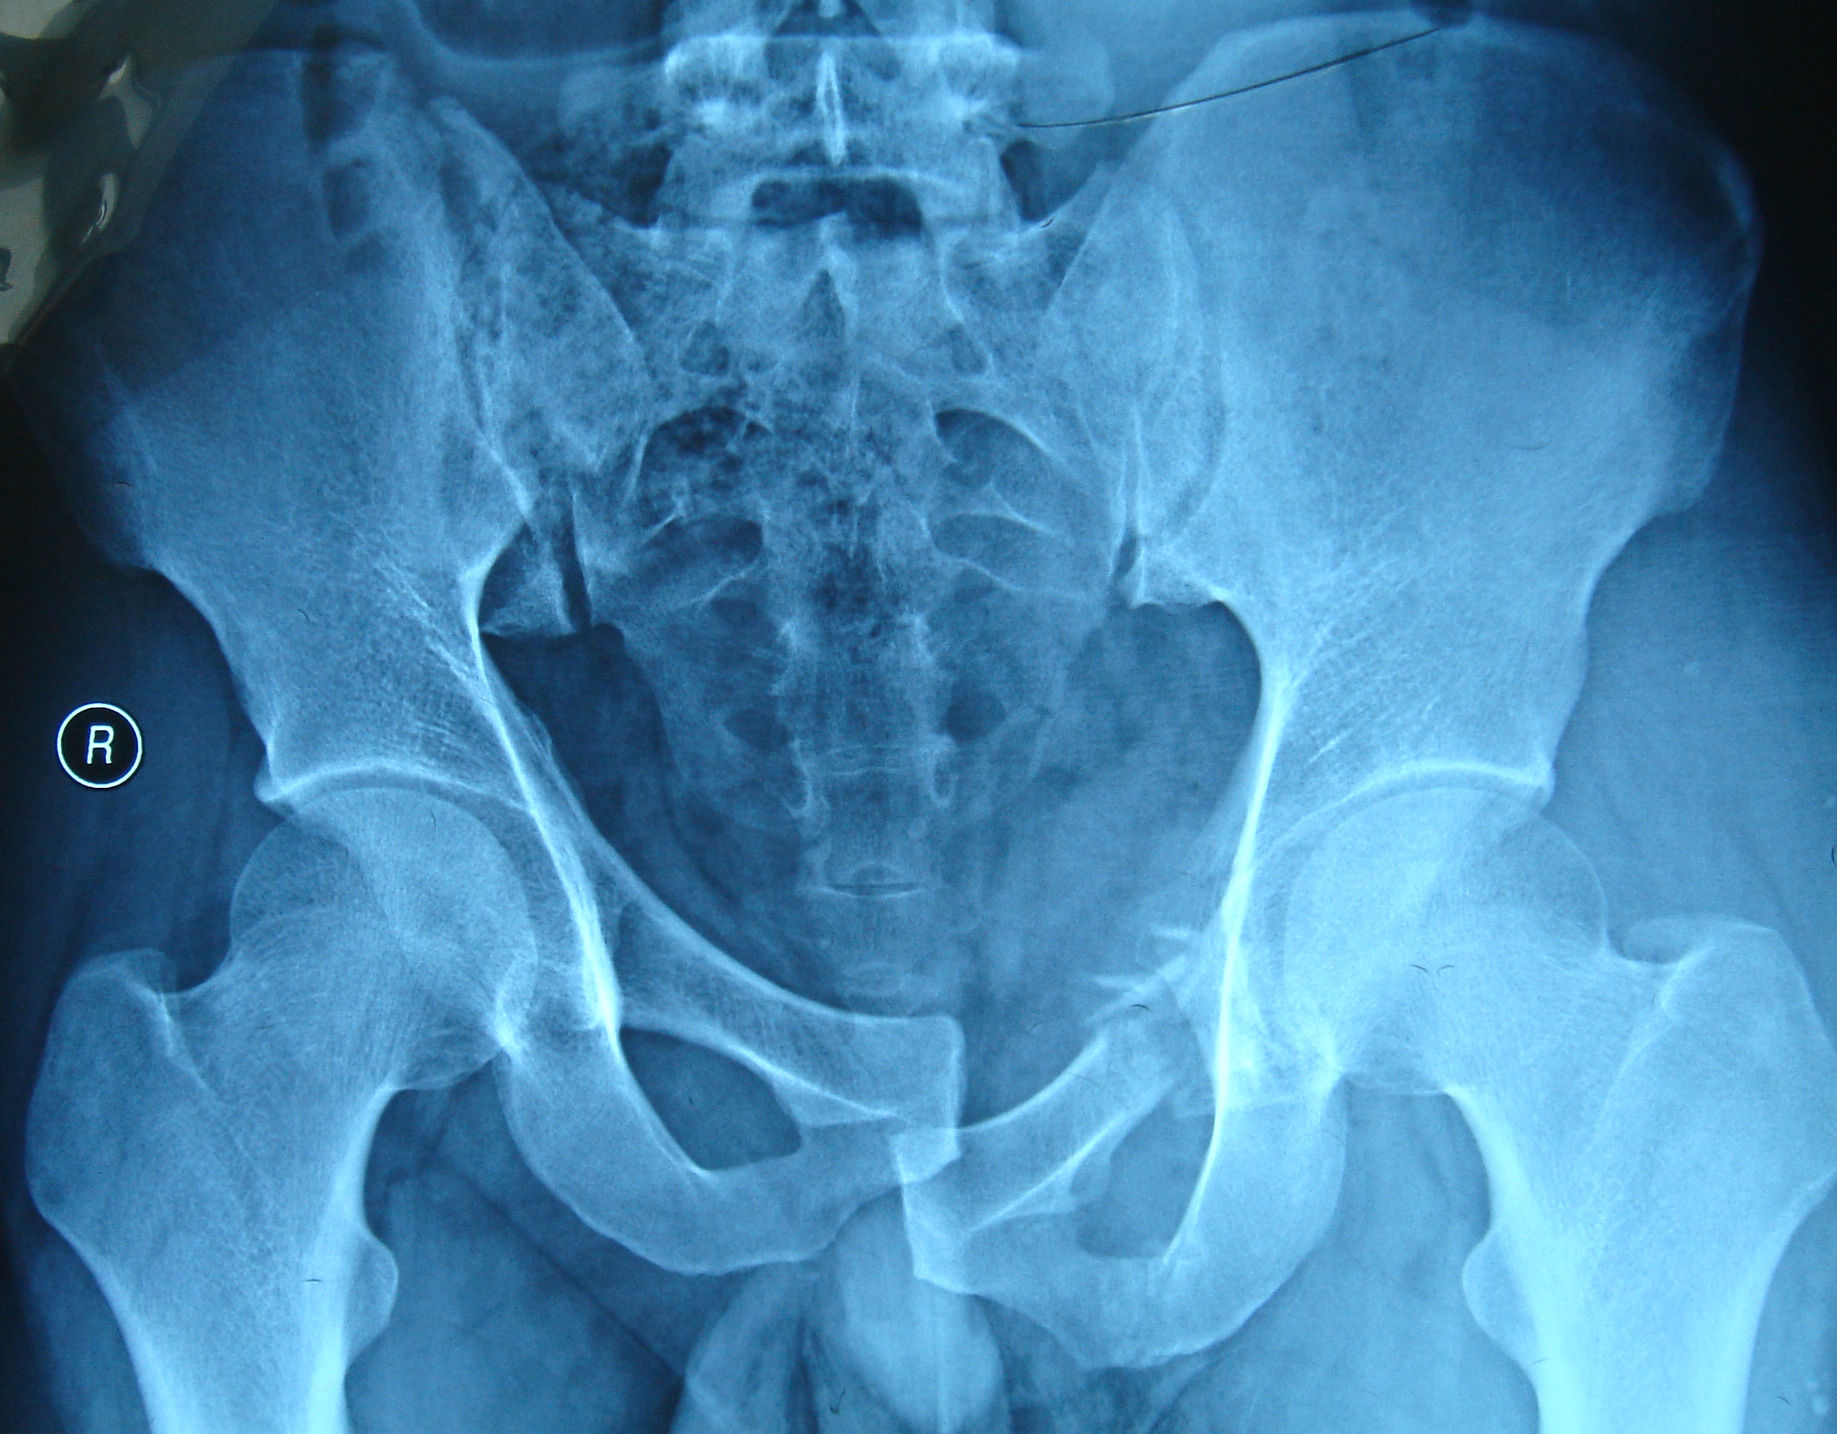

表现骨盆骨折出血量通常很大,可能导致患者出现面色苍白意识障碍等休克症状处理措施需要立即就医,进行输血或补液治疗,以纠正休克状态神经损伤影响骨盆骨折可能导致神经受损,进而造成下肢麻痹或感觉障碍处理措施神经损伤需要及时诊断和治疗,以恢复神经功能或减少后遗症功能障碍表现骨盆;1 休克 由于骨盆血供丰富,骨折后出血量大,可能达到5000ml,导致休克 休克表现为面色苍白全身大汗皮肤湿冷以及血压降低2 局部肿胀 骨盆骨折后,局部出血并积聚,造成肿胀现象3 神经损伤症状 骨盆内有重要的神经如股神经坐骨神经骶髂神经,这些神经可能被骨折断端损伤 神经损伤表现为;骨盆挤压分离试验可能为阴性影像学检查需通过X线或CT检查确诊与股骨转子间骨折的鉴别压痛点股骨转子间骨折的压痛点主要位于大转子骨盆挤压分离试验同样可能为阴性影像学检查确诊也需依赖X线或CT检查综上所述,骨盆骨折的鉴别诊断需结合患者的临床表现体征及影像学检查进行综合判断。

骨盆骨折的并发症主要包括以下几点失血性休克最常见且最严重骨盆是松质骨,骨折后松质骨血运丰富,容易导致大出血,形成腹膜后血肿,进而引发失血性休克盆腔内脏器损伤膀胱损伤常见表现为血尿女性卵巢及子宫损伤会导致出血情况骶丛神经损伤骨折移位明显时可能导致骶丛神经损伤,引起神经;异常活动髂骨翼或骶骨尾骨发生骨折后,检查时会在局部出现反常活动,即骨头出现不正常活动骨盆挤压分离试验阳性骨盆发生骨折后,向内或向外按压骨盆会出现疼痛休克表现骨盆骨折容易合并大失血,患者会出现面色苍白表情淡漠皮肤湿冷血压下降尿量减少等休克症状感染症状骨盆骨折容易损伤膀胱。

成因骨盆骨折一般是在车祸塌方或战争火器伤等强烈外力作用下造成的伴随伤势骨盆骨折通常伴有全身的多发伤因此,在治疗骨盆骨折时,也需要重视患者其他部位的伤势情况分类A型主要是耻骨下支骨折B型由耻骨联合骨折分离造成的损伤C型表现为双下肢长短不一骨盆倾斜以及髋臼的损伤等复杂;骨盆骨折的临床表现主要包括以下几点疼痛患者通常会出现下腹部和会阴部的疼痛查体时可发现触痛会阴部瘀斑会阴部可能出现瘀斑,这是骨折部位出血渗透到皮下组织所致骨盆分离挤压试验阳性进行骨盆分离挤压试验时,患者会出现疼痛加剧的症状,这是骨盆骨折的重要体征下肢不等长患者可能出现两侧;原因骨盆骨折造成膀胱损伤,愈合后可能出现相关症状表现排尿困难以及尿道口溢血小腿肌肉肌力减退和感觉减退原因骨盆骨折导致神经损伤后果受损神经支配的小腿肌肉肌力减退,同时感觉功能也会减退综上所述,骨盆骨折的后遗症可能涉及髋关节稳定性泌尿系统功能以及下肢神经功能等多个方面因此;1 内脏损伤 直肠破裂骨盆骨折断端可能移位并损伤直肠 膀胱破裂和尿道断裂同样,骨折断端可能损伤膀胱和尿道,引发尿液外渗和盆腔感染2 失血性休克 内出血骨盆骨折可能导致髂内外动脉和静脉损伤,引起大量内出血 休克表现病人可能出现面色苍白表情淡漠皮肤湿冷血压下降尿量减少等休克;骨盆骨折的临床表现主要包括以下几点大量失血与休克主要症状骨盆骨折常导致大量失血,严重者可迅速出现休克症状髋关节疼痛疼痛特点患者会感到髋关节部位明显的疼痛,疼痛程度与骨折的严重程度相关骨盆挤压分离试验阳性试验方法进行骨盆挤压或分离试验时,患者会出现疼痛加剧或骨盆不稳定的表现;骨盆骨折的常见并发症主要包括以下几点出血性休克原因严重的骨盆骨折可能导致大量出血,尤其是当骨折错位严重或多处骨折时表现患者会出现低血压症状,严重时可能危及生命神经损伤受损神经坐骨神经骶神经或股神经可能受损表现受损神经支配的肢体远端可能出现麻木和肌无力症状内脏损伤受。